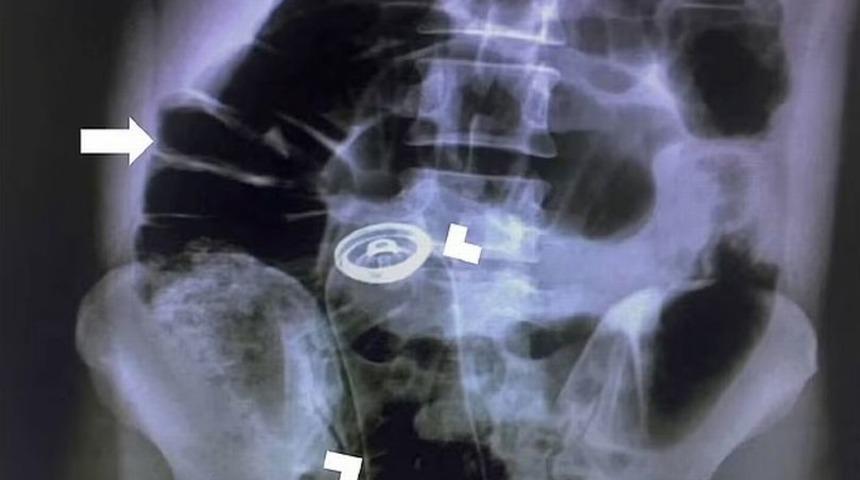

İran’da ismi açıklanmayan 30 yaşındaki bir adam şiddetli karın ağrısı ve dayanılmaz yanma hissi nedeniyle hastaneye başvurdu. Yapılan incelemelerin sonucunda röntgende adamın anüsüne sıkışan yabancı bir cisim tespit edildi. 30 yaşındaki adam acilen ameliyata alındı. Hastanın herhangi bir komplikasyon yaşamadan sağlığına kavuştuğu ifade edildi.

İran’da yaşayan 30 yaşındaki ismi açıklanmayan bir hasta mide ağrısı ve acı hissiyle acile servise başvurdu. Doktorlar ağrı ve acının nedenini tespit edebilmek için bir dizi inceleme yaptı. Sonunda ise söz konusu ağrı ve acının arkasında anüse sıkışan yabancı bir cisim olduğu tespit edildi. Yakın zamanlı bir tıp dergisinde yer alan rapora göre, 30 yaşındaki hastanın anüsünde bir deodorant şişesinin sıkıştığı belirtildi.

Daily Mail’de yer alan habere göre doktorlar cerrahi prosedürü devreye sokarak hastanın midesini kesip sıkışan yabancı cismi çıkarttı. Tahran Tıp Bilimleri Üniversitesi'nde gerçekleşen işlemin sonrasında bir gün hastanede kalan adam taburcu oldu.